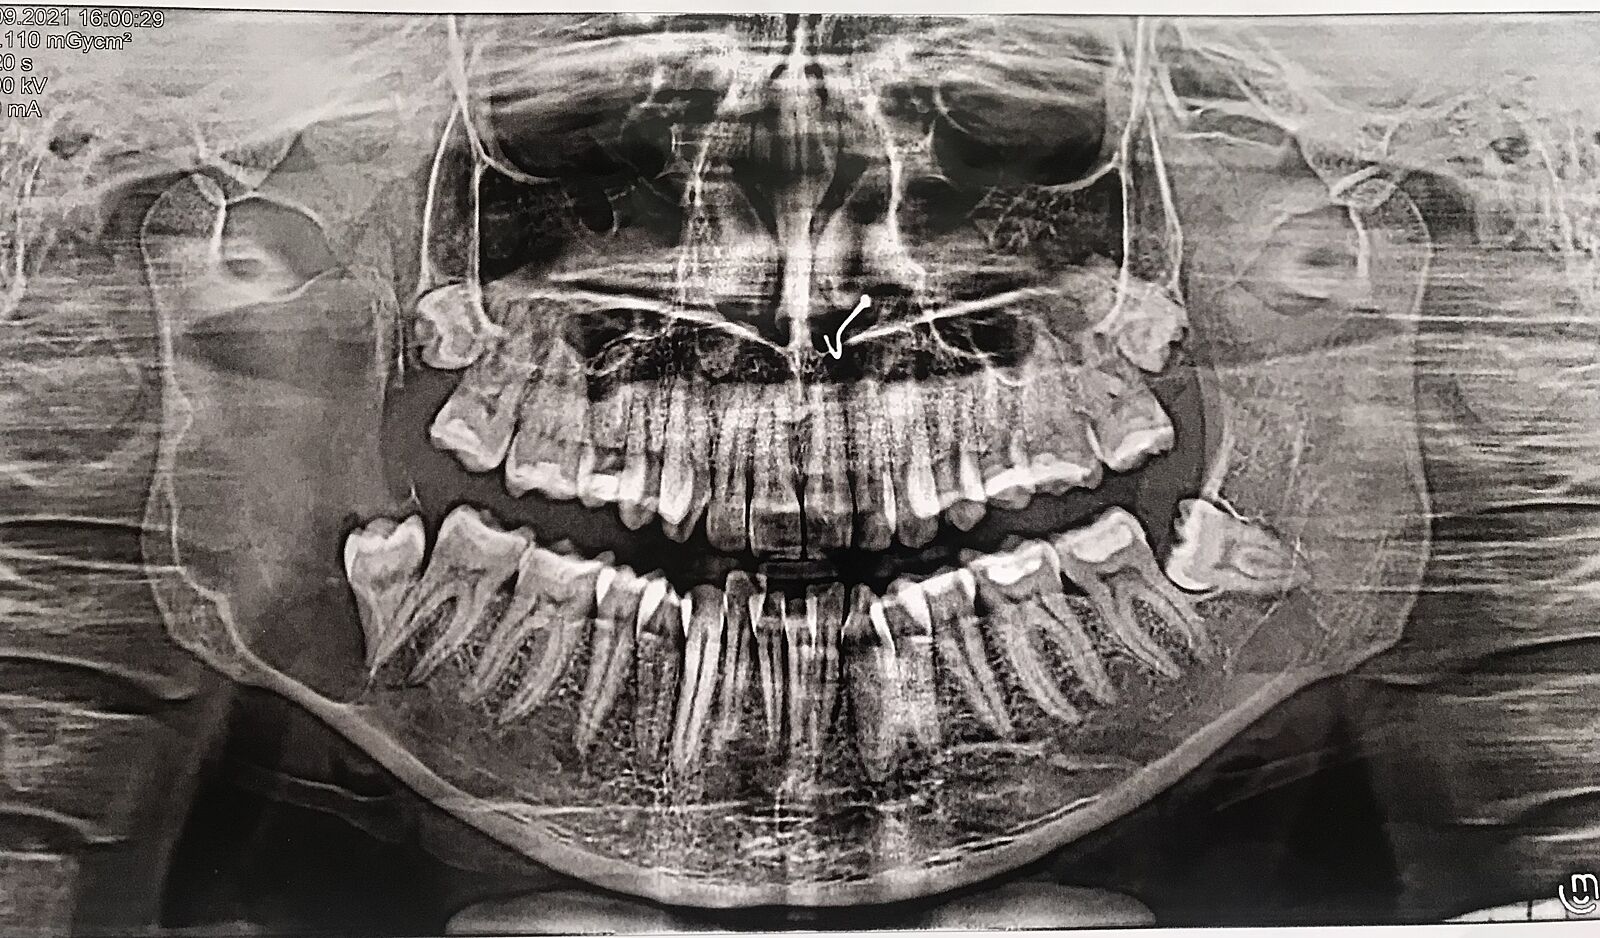

Кто удалял фолликулярную кисту зуба (большого размера)

Посоветуйте челюстно лицевого хирурга , для удаление кисты

Нужно будет наращивать кость.